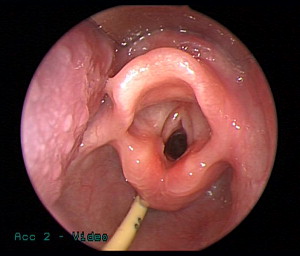

Microlaryngoscopy is performed with a rigid anterior commissure-type laryngoscope such as a Benjamin or Parsons placed in the vallecula ( Fig. 2 ) and used to expose the endolarynx and subglottic airway. This will reveal a subglottic hemangioma just below the vocal cords ( Fig. 3 ). Magnification from a Storz Hopkins telescope is used to visualize the subglottic airway and the scope can be passed down to the level of the carina. It is important to carefully look at the trachealis muscle in the back wall of the trachea for staining, fullness, and signs of vascular disease ( Fig. 4 ). Tracheal hemangioma may be subtle and its treatment is challenging.